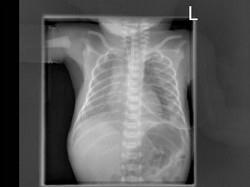

出生一天的早产儿,呼吸窘迫,请结合图片选出最可能的诊断 ( )A、肺气肿B、气胸C、肺气肿D、肋骨骨折E、湿肺

问题 出生一天的早产儿,呼吸窘迫,请结合图片选出最可能的诊断 ( )

选项 A、肺气肿 B、气胸 C、肺气肿 D、肋骨骨折 E、湿肺

答案 B